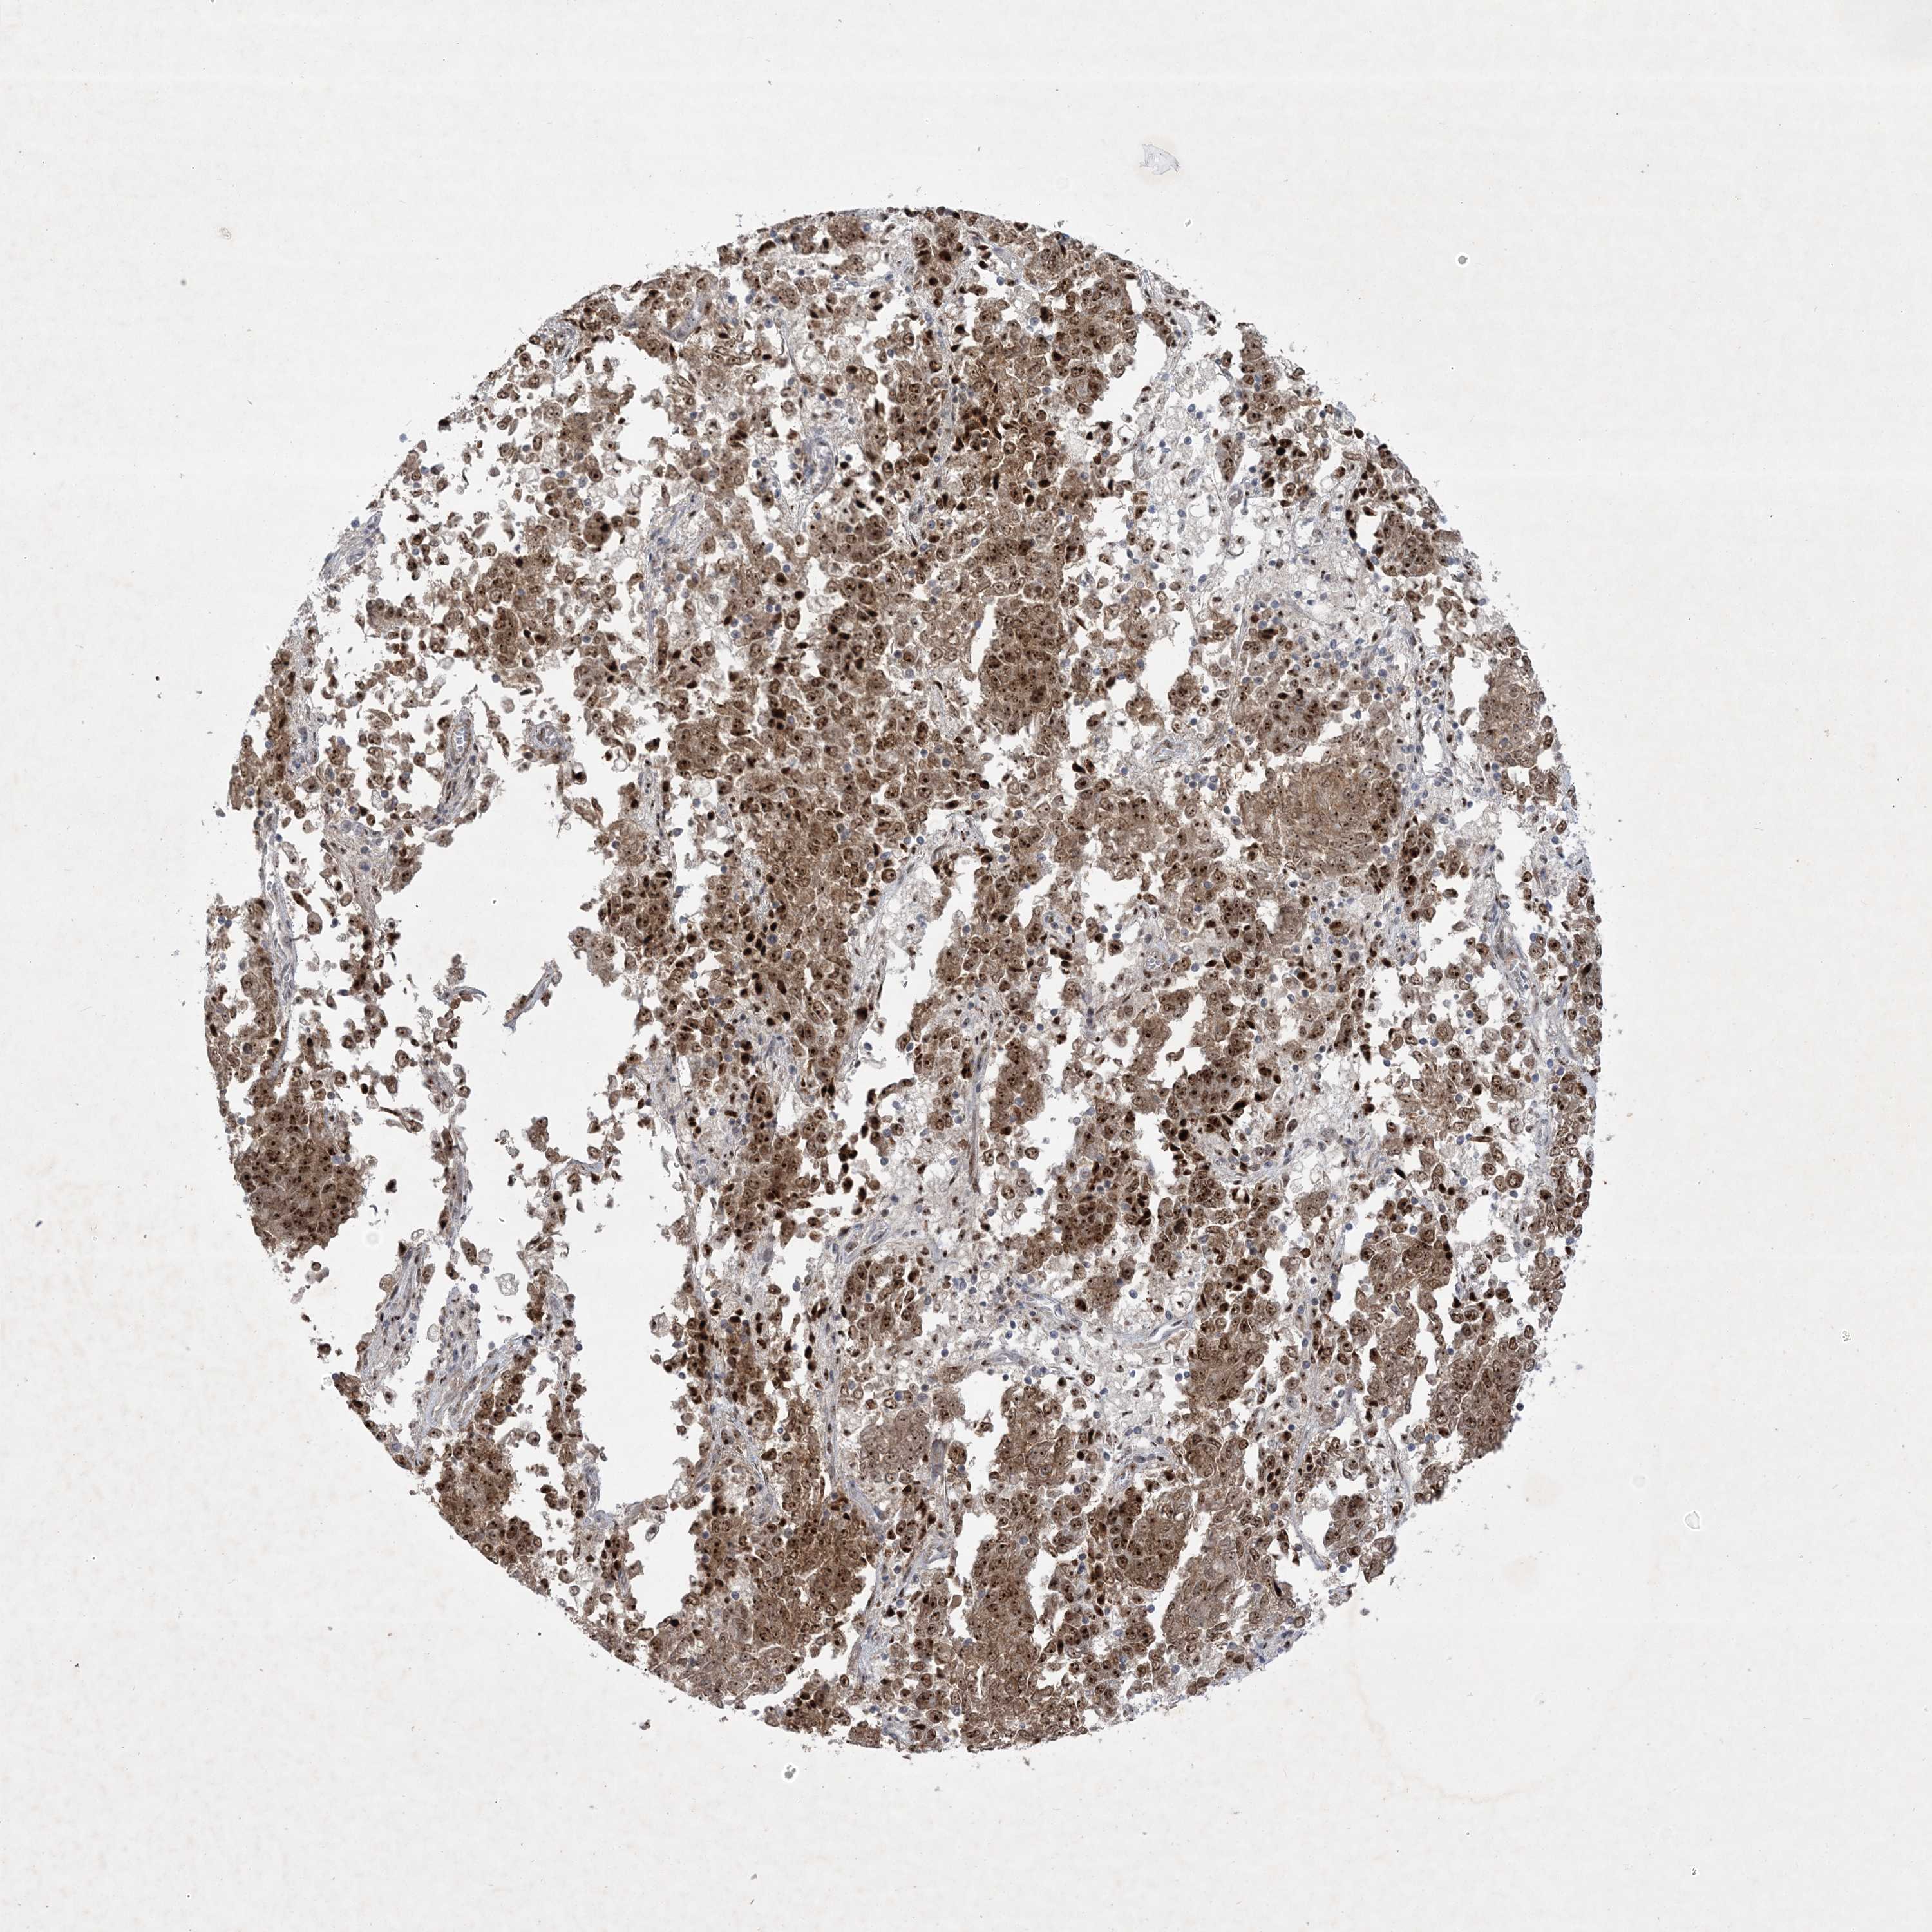

ENDOMETRIAL CANCER - Protein expressioni

A mouse-over function shows sample information and annotation data. Click on an image to view it in a full screen mode. Samples can be filtered based on level of antibody staining by selecting one or several of the following categories: high, medium, low and not detected. The assay and annotation is described here.

Note that samples used for immunohistochemistry by the Human Protein Atlas do not correspond to samples in the TCGA dataset.

Antibody stainingi

Antibody staining in the annotated cell types in the current human tissue is reported as not detected, low, medium, or high, based on conventional immunohistochemistry profiling in selected tissues. This score is based on the combination of the staining intensity and fraction of stained cells.

Each image is clickable and will lead to virtual microscopy that enables deeper exploration of all samples and also displays staining intensity scores, fraction scores and subcellular localization as well as patient and tissue information for each sample.

Antibody HPA036295

Antibody HPA036296

Staining

High

Medium

Low

Not detected

Intensity

Strong

Moderate

Weak

Negative

Quantity

>75%

75%-25%

<25%

None

Location

Nuclear

Cytoplasmic/membranous

Cytoplasmic/membranous,nuclear

Adenocarcinoma, NOS

Adenocarcinoma, metastatic, NOS